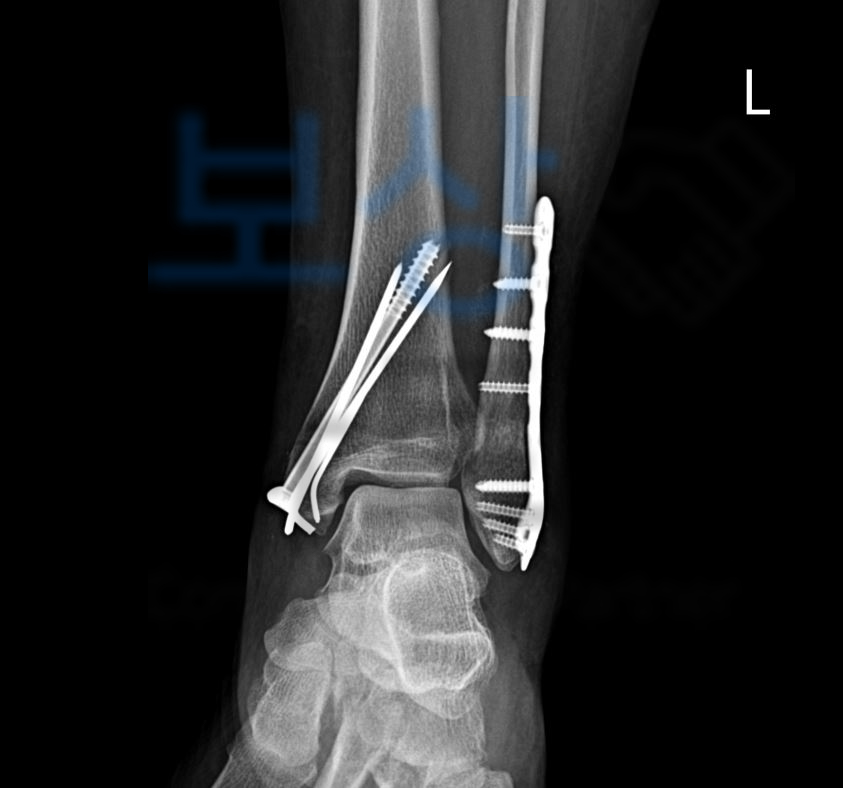

Lt. ankle pain 왼쪽 발목 통증 정밀검사를 받아보니 아래의 사진처럼 흔히 말하는 발목의 복숭아뼈가 골절되어 수술이 불가피 했습니다.

좌측 족관절의 외복사골절, 관혈적 정복 및 금속판 내고정술

의뢰인읜 양측의 복사골절 즉 외복사, 내복사 또는 양과 골절 수술받아 6주 이상의 입원 및 재활치료를 받아야 했죠. 의뢰인은 보상파트너의 도움을 받아 가입하신 보험증권에서 상해후유장해 항목을 찾으셨습니다.